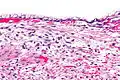

| Micrograph showing a mucinous cystadenoma of the ovary. H&E stain. | |

Microscopy